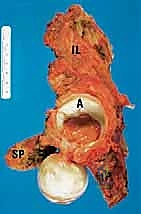

FIG 1 • The bony pelvis and its relation to the major blood vessels, nerves, and visceral organs.

* CT with Intravenous Contrast and 3D Reconstruction (FIG 3): This is our workhorse for assessing bone involvement, destruction, and the critical relationship between the tumor and major pelvic blood vessels. It reveals any distortion of the pelvic anatomy and guides resectability. Figure 3A clearly shows extensive bone destruction and tumor extension into the pelvis and gluteal region. Figure 3C highlights an extensive tumor on the medial aspect of the ilium with destruction of the inner table.